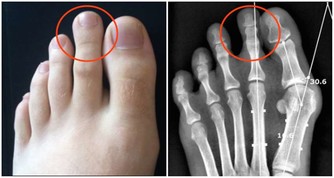

肝臟對鐵的代謝起著重要作用,平時肝臟內積蓄有鐵成份。肝細胞遭到破壞的話,肝細胞內的鐵會流入血管,使血液內鐵成份增加,導致臉色發黑。這種症狀最容易在男性和閉經後的女性身上出現。因此,當出現臉色發黑徵兆時,一定要警惕是否肝受損了,並要及時護肝。